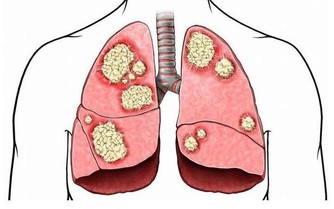

不吃早餐最直接的就是會傷害胃部健康。經過一夜的分解、消化,此時的胃酸濃度很高,而如果不吃早餐,飢餓就會使得胃酸持續分泌長期不吃早餐會造成胃酸持續傷害胃黏膜,很容易出現胃炎、胃潰瘍等腸胃疾病。